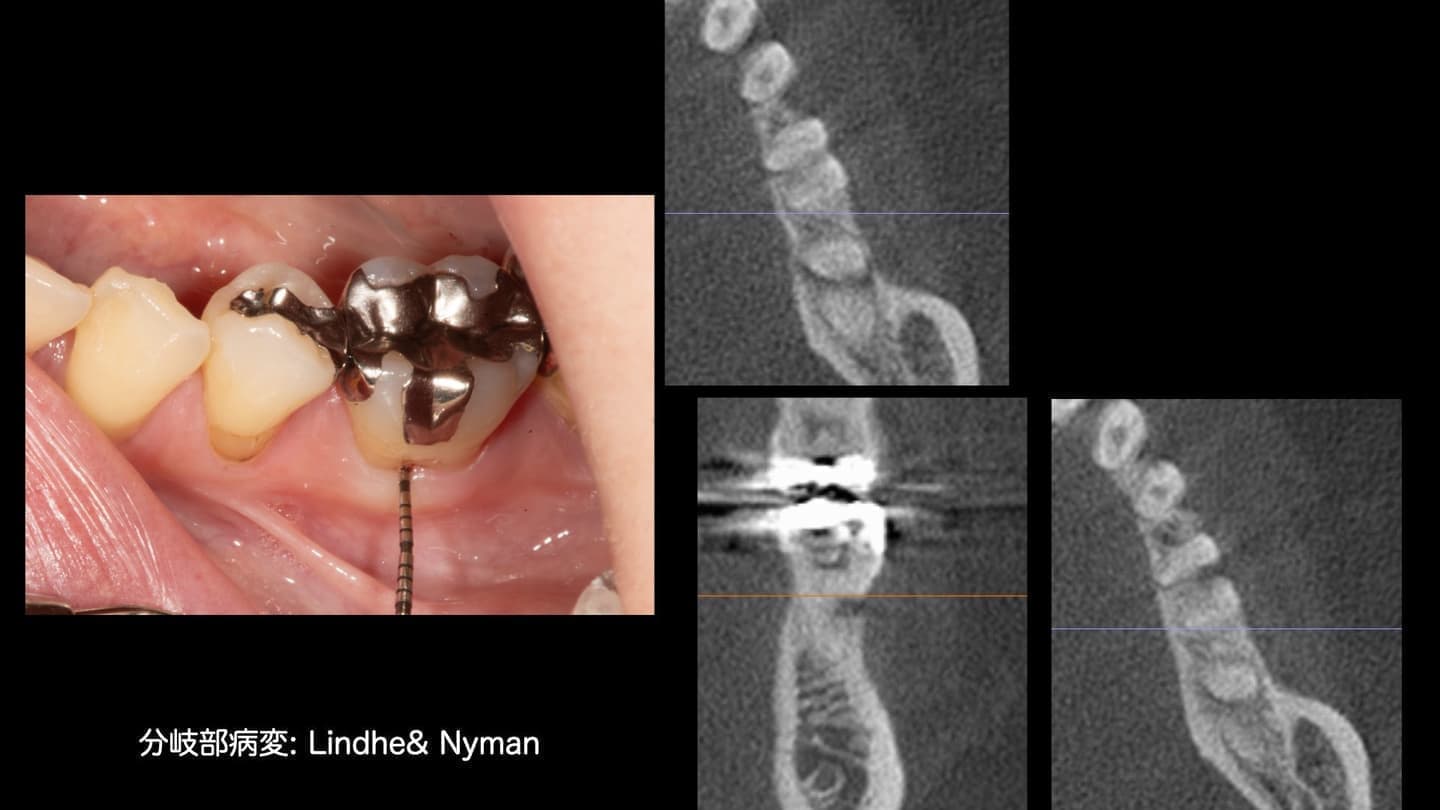

基本的な検査だけでなく、CT検査、歯周病に特異的な細菌のPCR検査、噛み合わせの検査、生活習慣の見直しなどを行います